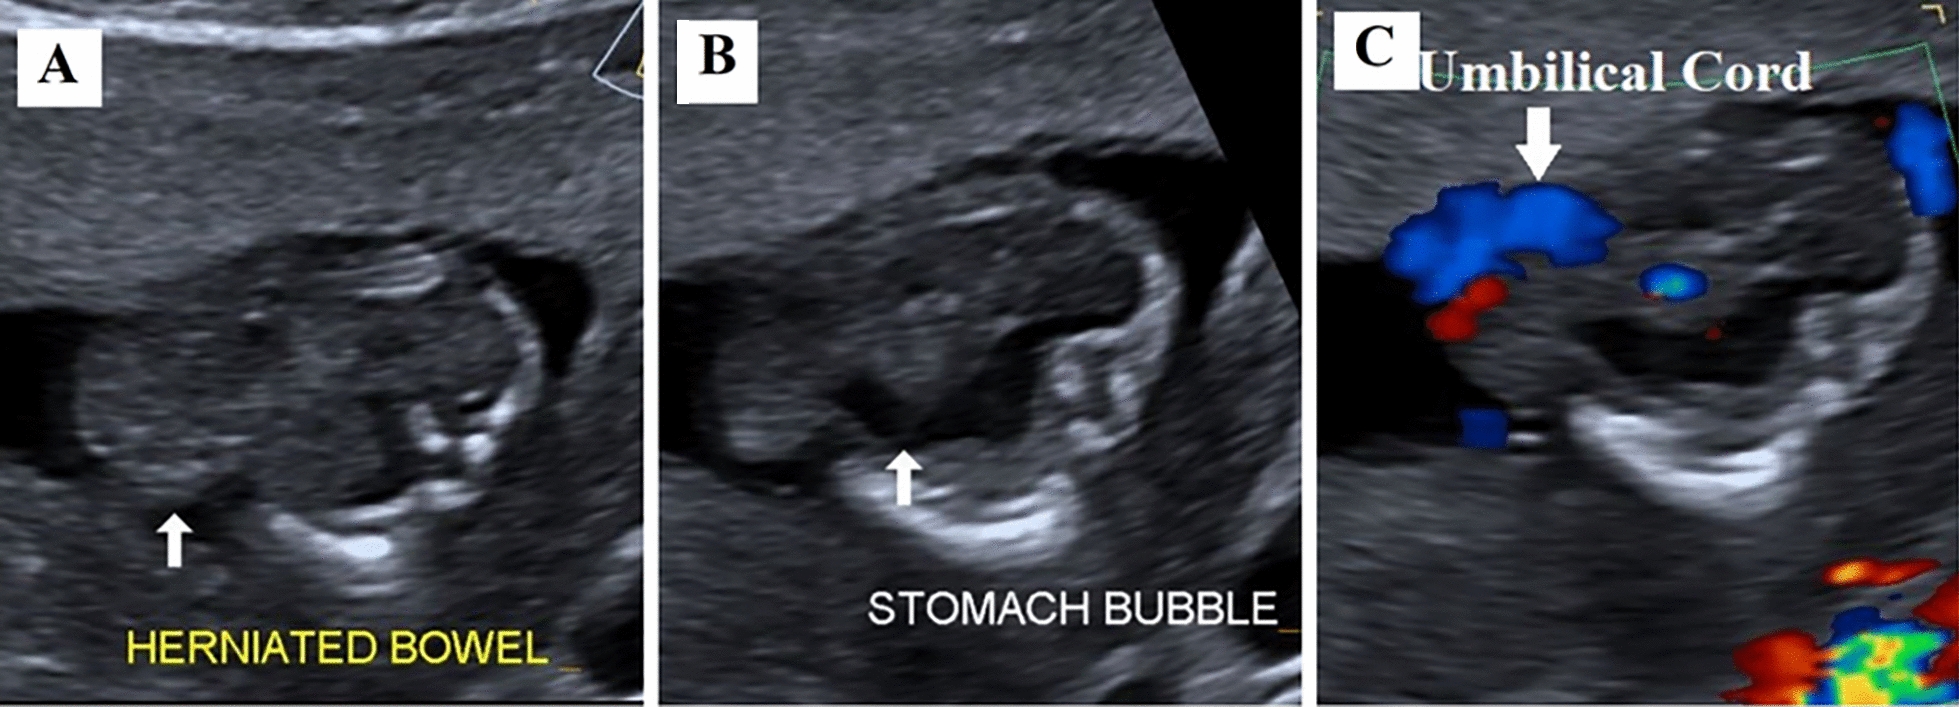

Case report: This report presents two cases: one of true omphalocele in a twin pregnancy and another of pseudo-omphalocele, underscoring the importance of careful assessment. The first case involves a twin pregnancy at 12 weeks' gestation, conceived through assisted reproductive technique in a 38-year-old Nepali woman of Indo-Aryan ethnicity. During a routine check-up, one twin was diagnosed with omphalocele. Trans-abdominal fetal reduction of the anomalous twin was performed. The other twin progressed to term and was delivered via cesarean section at 39 weeks. The second case involved pseudo-omphalocele, observed at 15 weeks' 3 days of gestation in a 32-year-old Nepali woman of Tibeto-Burmese ethnicity. Initially, the fetal abdomen appeared to herniate, mimicking omphalocele. However, a repeat examination after 30 min showed no herniation or defect. Retrospective analysis revealed that the misdiagnosis occurred because the fetal abdomen was compressed between the contracted myometrium and placenta.